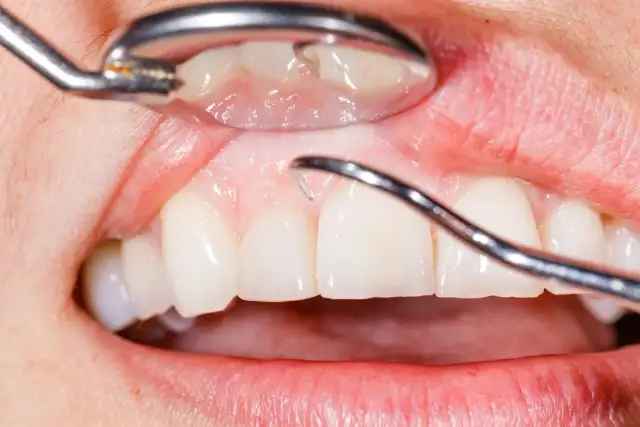

Podrażnione dziąsła? Odkryj domowe sposoby na szybką ulgę, skuteczne leki z apteki i dowiedz się, kiedy iść do dentysty. Sprawdź nasz poradnik!